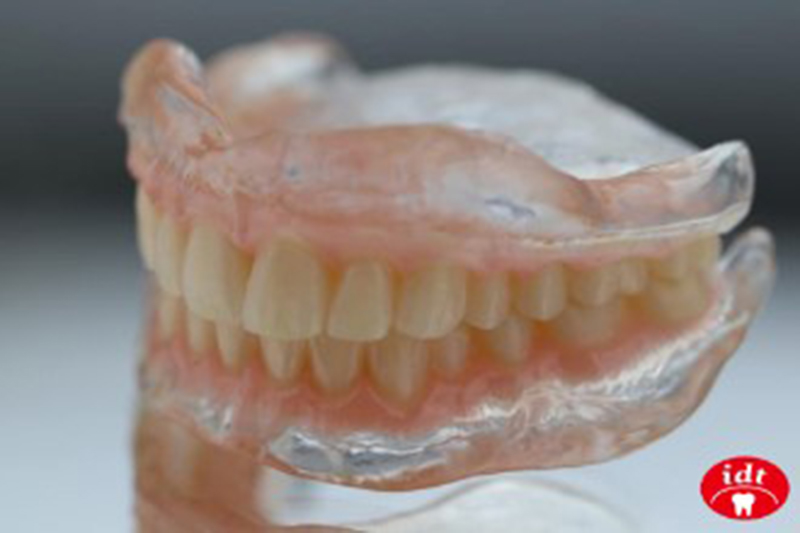

治療型義齒,又稱為「復健型義齒」。

它能幫助病患調整口內咬合、硬軟組織、顎間關係到穩定狀況,對於剛拔牙完或長期全口無牙的患者,是必須經歷的復健過程。